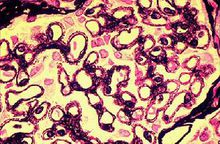

1.光鏡系膜細胞的瀰漫性增生為系膜增生性腎小球腎炎的基系膜增生性腎小球腎炎理特點,可伴有系膜區的增寬。此病變通常影響80%以上的腎小球,多數腎小球病變程度相似,稱為瀰漫性增生。早期以系膜細胞數增多為主,在中等病變中每個系膜區的系膜細胞數為4~5個。而在較嚴重的病變中,每個系膜區的系膜細胞數多在5個以上,系膜區還可見單核細胞浸潤。Masson染色約50%的病例可見系膜區嗜復紅免疫複合物沉積。腎小球毛細血管壁正常,毛細管腔開放較好。大多數病例腎小管、間質組織及腎內小動脈正常。

3.免疫螢光主要有4種表現:①以IgM為主的免疫球蛋白伴或不伴C3沉積,系膜區常有IgM沉積。②58%的患者有IgG和C3沉積。③僅有補體C3沉積。④無任何沉積物,免疫病理檢查陰性。